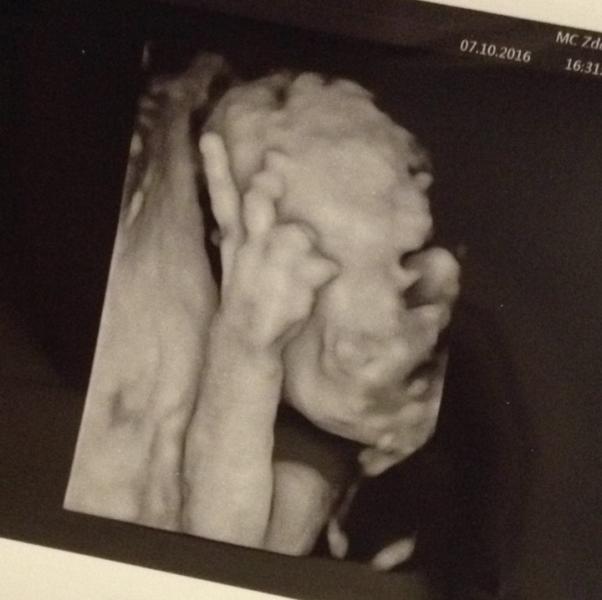

post image

Как же это милооо😭🔆🔆🔆🍩@gigil @dostupzakrit гоголики такие, эти жесты на всю жизнь запоминаются❤️🌞

@marryme, а мой кулачок показал😂

А моя фигу показывала 😂

Мне так смешно было там😁столько ждала этого узи, и такой жест как только увидела его😹@busya_ @tytysik